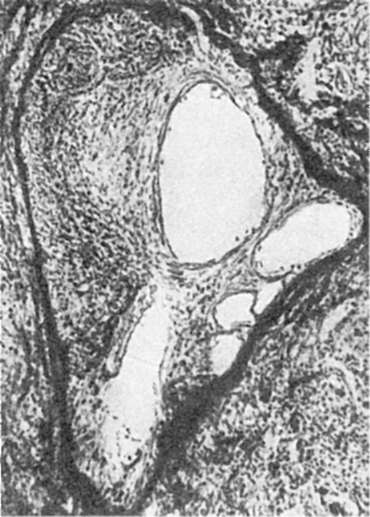

Организация. Организацией, которая является одним из проявлений адаптации, называют замещение участка некроза или тромба соединительной тканью, а также инкапсуляцию.

Замещение участка омертвения или тромботических масс соединительной тканью (собственно организация) происходит в том случае, когда массы подвергаются рассасыванию и одновременно в них врастает молодая соединительная ткань, превращающаяся затем в рубцовую. Об инкапсуляции говорят в тех случаях, когда омертвевшие массы, животные паразиты, инородные тела не рассасываются, а обрастают соединительной тканью и отграничиваются от остальной части органа капсулой. Массы некроза могут пропитываться известью - возникают петрификаты. Иногда во внутренних слоях капсулы путем метаплазии происходит образование кости. Вокруг инородных тел и животных паразитов в грануляционной ткани могут образовываться многоядерные гигантские клетки (гигантские клетки инородных тел), которые способны фагоцитировать инородные тела

Организация и канализация тромба вены